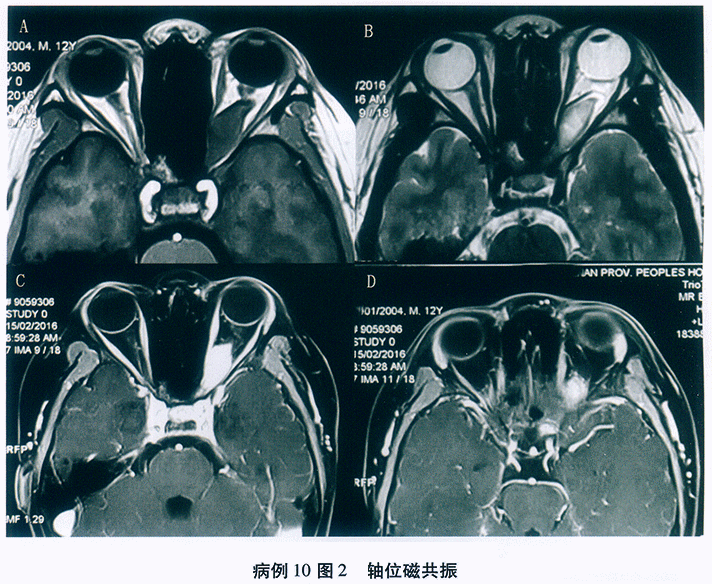

晶状体厚度测量:右眼: 5.4mm;左眼5.5mm。

超声生物显微镜检查(UBM): 双眼前房深度:R: 0.65mm/L1.22mm。双眼晶状体呈球形(见图18-4),右眼鼻侧及鼻下方, 左眼鼻上、鼻侧及鼻下方见晶状体悬韧带稀疏,悬韧带拉长明显。右眼鼻下、下方见房角开放, 余各方位均见虹膜小梁网接触。左眼各方位均见虹膜小梁网接触(见图18-5)。

(4)裂隙灯检查发现前房极浅,以中央前房浅明显。散瞳后可见晶状体呈球形,前突,悬韧带拉长,稀疏,伴晶状体脱位。

(5)A超测量晶状体厚度较厚,超声生物显微镜检查可见晶状体呈球形,不同方位虹膜小梁网接触,房角关闭,晶状体半脱位。

基于以上几点分析:初步诊断为球形晶状体、继发性闭角型青光眼。